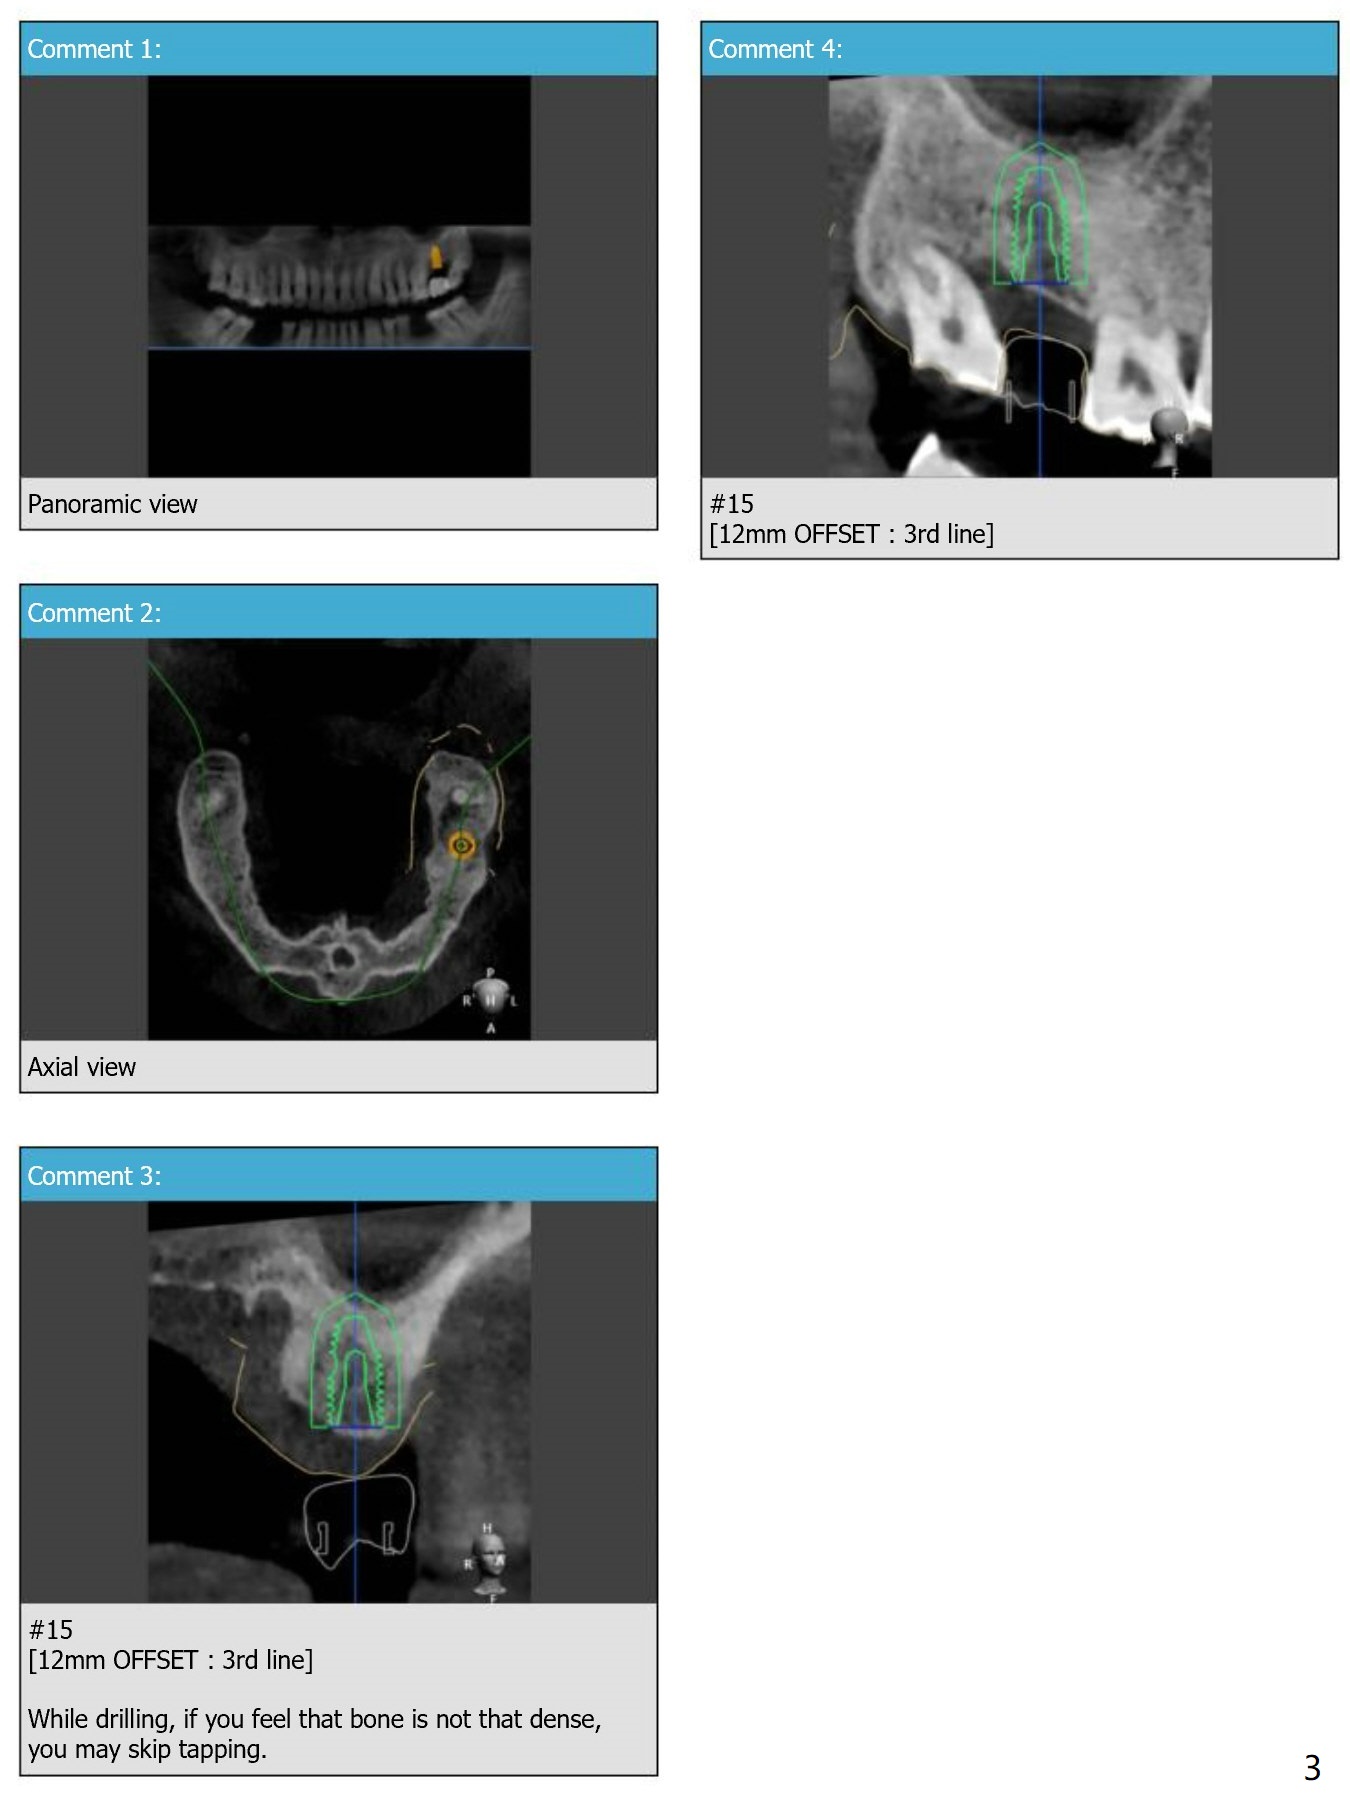

To answer your first question, yes, 12mm offset has been set up due to narrow mesiodistal space and position of #16 leaning towards mesial.

Please refer to the picture below.

Secondly, No, for this time, there's sufficient bone in height, so there's no need to go for short drills such as 7.3 and 8.5mm (I mean as a final drill, Of course, those short drills are part of drilling sequence). And this case won't require sinus elevation therefore you can go with regular drilling sequence.

When I reviewed this case, the bone density was high compared to other upper molar cases. So, as we have agreed on our phone call, we will not go with undersized drilling this time and if there's lots of torque being applied, then you may also conduct tapping.

As we know that the final drill would be 4.5 X 10mm to place 5.0 X 10.0mm implant. (Usually drill size is 0.5mm smaller than the actual implant size and you may have noticed it before on the guide kit)

And with 4.5 X 10.0mm drill, as we have raised the sleeve level to 12mm offset which is 3mm higher. So, your final drill would be 4.5 X 13.0mm.

When you take a look at the sequence I sent you, our final drill is 4.5 X 11.5mm that is because this case was designed to go with 1 size shorter drilling in length in order not to perforate sinus membrane.

Last question was for the bone trimmer. OFFSET 12mm bone trimmer  is the longest bone trimmer we have in our kit and I have not faced any case requires longer bone trimmer than that. So I think it will be enough length to trim the cortical bone for this case.